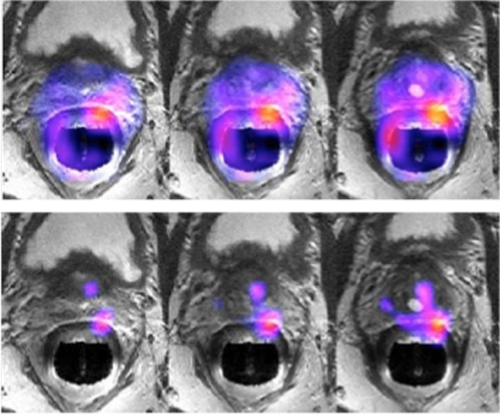

The four images demonstrate dynamic T1 imaging with PB Navigator, which enables the patient to breathe freely while capturing contrast in fast temporal phases. Whole spine evaluation can be obtained simply with routine T2 frFSE imaging.